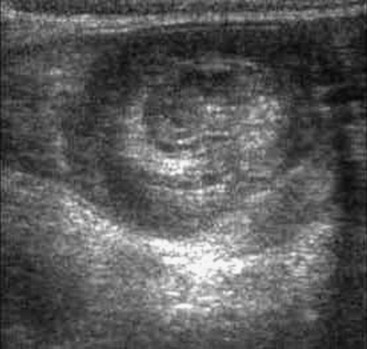

The use of abdominal ultrasound (US) for the evaluation of intussusception was first described in 1977.20 Since then, most institutions have adopted it as a screening tool because of the lack of radiation exposure, ability to identify pathologic lead points, and decreased cost.21,22 The characteristic finding on ultrasound has been referred to as a ‘target’ or ‘doughnut’ lesion (Fig. 38-4), which consists of alternating rings of low and high echogenicity representing the bowel wall and mesenteric fat within the intussusceptum in a transverse plane. The ‘pseudokidney’ sign is seen on longitudinal section (Fig. 38-5). This pattern is secondary to the edematous walls of the intussusceptum within the intussuscipiens. Ultrasonography can also guide the therapeutic reduction of an intussusception.21 Equivocal findings using this modality should mandate a conventional contrast or air enema.23